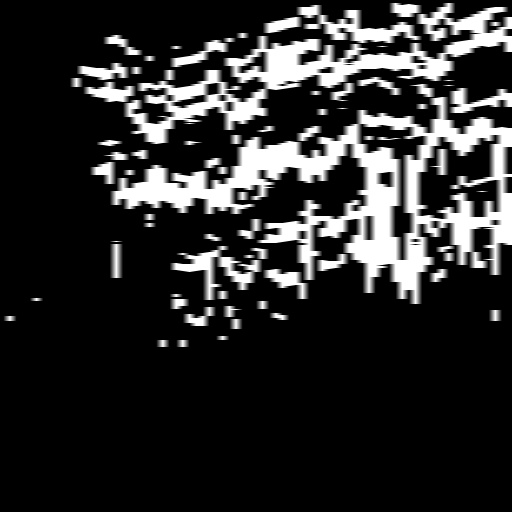

4.1 XACV Dataset

We collect 111 complete records of coronary artery X-ray videos, encompassing the injection, flow through the blood vessels around the heart, and dissipation of the contrast agent. Subsequently, we establish the XACV (X-ray Angiography Coronary Video) dataset. Each video consists of varying numbers of high-resolution coronary artery X-ray images. We invite experienced radiologists to annotate the vascular regions, focusing on one or two frames where the contrast agent is most prominent in each video. The XCAD dataset contains only a single image, and the CADICA video dataset does not provide corresponding ground truth. Therefore, in the following experiments, we conduct all the analyses on our collected XACV dataset and the corresponding GT for each sequence. In Figure 5, we show that compared to other publicly available datasets, XCAD [33] and CADICA [19], our dataset exhibits finer annotations in the vascular regions, providing an advantage for future related tasks. The development and use of our dataset have been approved by our institution’s IRB.